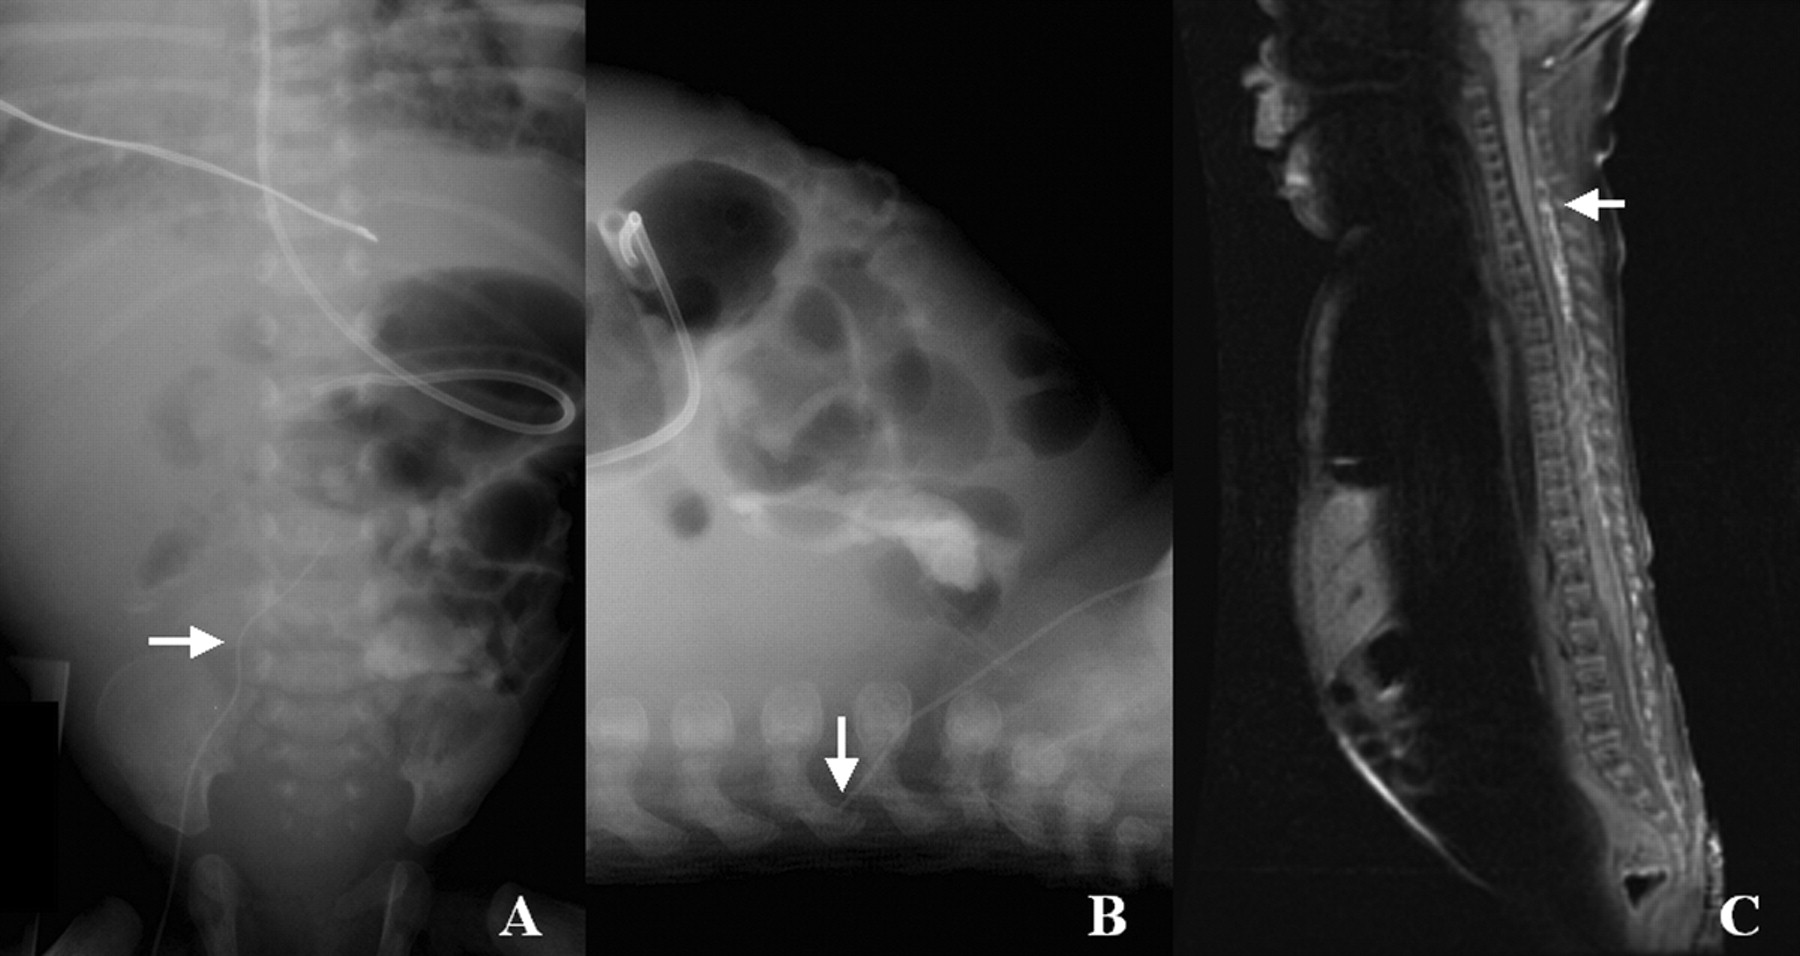

一个7-week-old ex-33-week女孩发烧和癫痫发作。血液和尿液培养结果为阴性。腰椎穿刺显示正常的乳白色液体,实验室值除了血糖升高(8867 mg / dL,问40到70 mg / dL)。腹部x光显示迁移的隐经皮中心静脉行(PCVL) (图)。核磁共振成像(图内)证明hyperintensity脊髓硬膜外神经丛。静脉输入营养液外渗到硬膜外腔在新生儿PCVLs是一种罕见的并发症。1PCVL进入提升的腰丛通过腰椎静脉连接在L4-5髂总静脉。